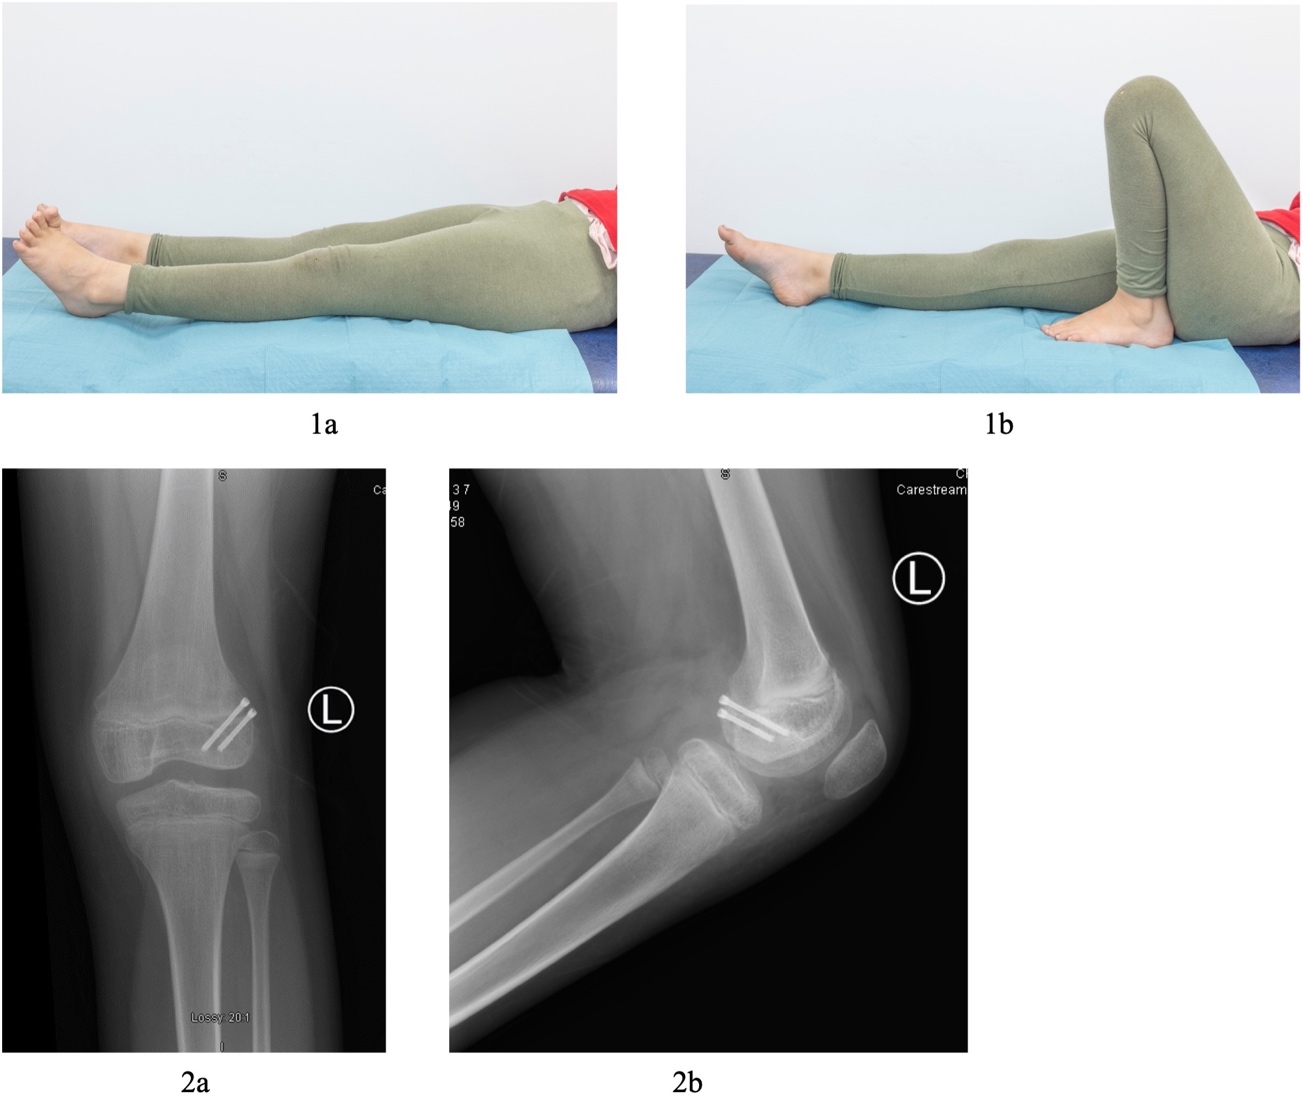

Initial lateral knee plain radiograph confirmed a large joint effusion with what looks like an associated rim of calcification posteriorly, while the anteroposterior (AP) radiograph was essentially normal with only subtle calcification around the lateral femoral condyle. (Fig 2)

Arthroscopy also revealed an area of chondral damage, at the level of the fracture line, for which micro-fracturing was performed. Reassessment of the patients ROM revealed flexion to 130° with an FFD of only 20°. Closure was performed in consecutive layers and the patient was placed in a hinged knee brace locked in 30° flexion. Postoperatively, the patient remained non-weight bearing for approximately six weeks with range of motion exercises starting two weeks post procedure. At five-month follow up this patient had full ROM and was mobilizing pain-free. She had returned to all regular daily activities including running and jumping comfortably. On examination there was no leg length discrepancy or angular deformity, and ROM was fully restored (0° to 140°) (Fig 5). Radiographs at 7 months postoperatively showed good alignment with no obvious physeal injury (Fig 5).

_radiographs_at_presentation_of_left_knee_(a)_anteroposterior_view_(b)_lateral_view._2)_.png)